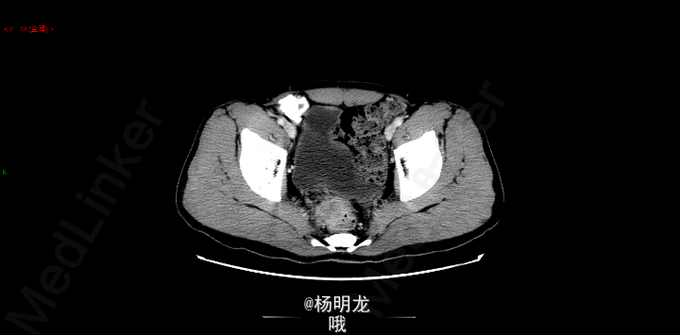

术前诊断 直肠癌 升结肠癌术后 双肺多发结节 转移瘤? 名称:开腹直肠癌切除,结肠造口术(Hartmann术) 探查:右上腹粘连,肝脏只探及部分,质地略韧,未触及肿物。直肠肿物上端位于盆底腹膜返折处,侵及腹膜,与左侧精囊粘连紧密。肿瘤4x4x3cm。无腹水,右腹部原术区未触及异常。 由于盆腔狭窄、粘连,向深部游离骶前间隙时出现静脉出血,紧急压迫止血。通过压迫不再出血后,于肿瘤上缘15 cm切断乙状结肠,于肿瘤下缘3cm以闭合器闭合直肠并切断直肠,切除肿瘤和肠管。 发生骶前静脉大出血,估计有2000ml。输血红细胞4u,血浆4u。